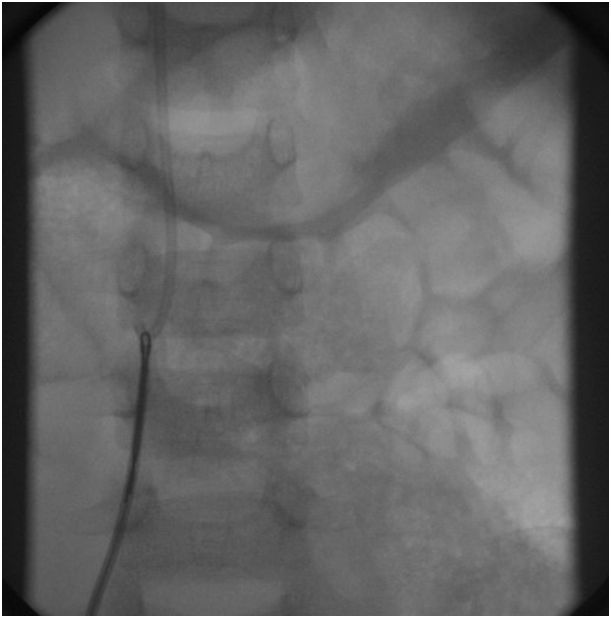

The Port-A-Cath was snared by 15mm loop (AMPLATZ GOOSE NECK). The snared Port-A-Cath could not be pulled into the MPA2 catheter. Consequently, both MPA2 catheter and snared Port-A-Cath were pulled through outside the heart with tight control on the snare to prevent it from slipping (Figure 6). There was no encountered resistance while pulling the Port-A-Cath, with stable hemodynamics. The child was extubated in the cardiac catheterization laboratory and recovered well from the procedure. A cardiothoracic surgeon has attended the operative theatre in case of any possible complication.

Figure 6 Shows removal of the catheter by loop-snare technique.